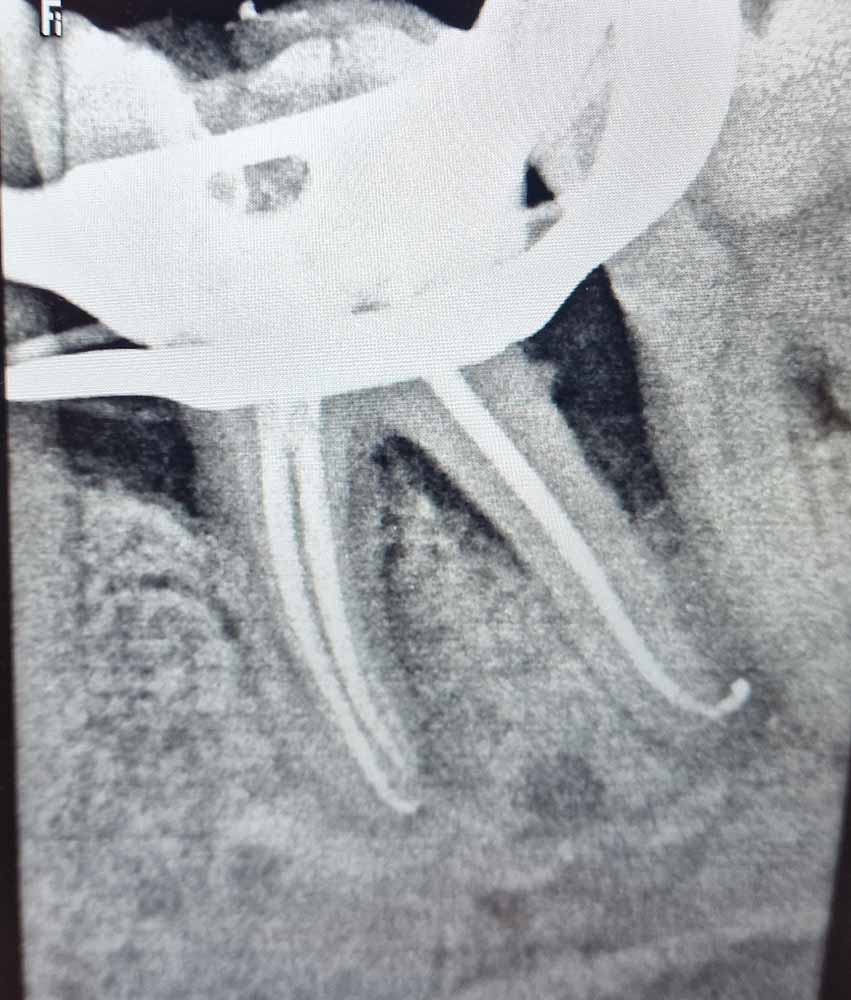

Ακολουθώντας τις πιο σύγχρονες τεχνολογικές εξελίξεις, έχουμε ενσωματώσει προηγμένα εργαλεία και μεθόδους στην ενδοδοντική θεραπεία. Χρησιμοποιούμε περιστροφικά εργαλεία τελευταίας γενιάς, σύγχρονα συστήματα έμφραξης με θερμοπλαστικοποιημένη γουταπέρκα, καθώς και ακριβείς συσκευές ανεύρεσης του μήκους των ριζικών σωλήνων, όπως το apex locator. Επιπλέον, η κλινική μας διαθέτει ψηφιακή ακτινογραφία και CBCT (αξονική τομογραφία) για την ακριβή διάγνωση και τον βέλτιστο σχεδιασμό της θεραπείας.

Ο συνδυασμός της τεχνολογίας με τη λεπτομερή προσέγγιση και την εξατομικευμένη φροντίδα που προσφέρουμε, μας επιτρέπει να επιτυγχάνουμε άριστα αποτελέσματα ακόμα και στις πιο απαιτητικές περιπτώσεις. Στόχος μας είναι η διάσωση των φυσικών δοντιών, διασφαλίζοντας τη μακροχρόνια υγεία και λειτουργικότητα του στόματος των ασθενών μας.